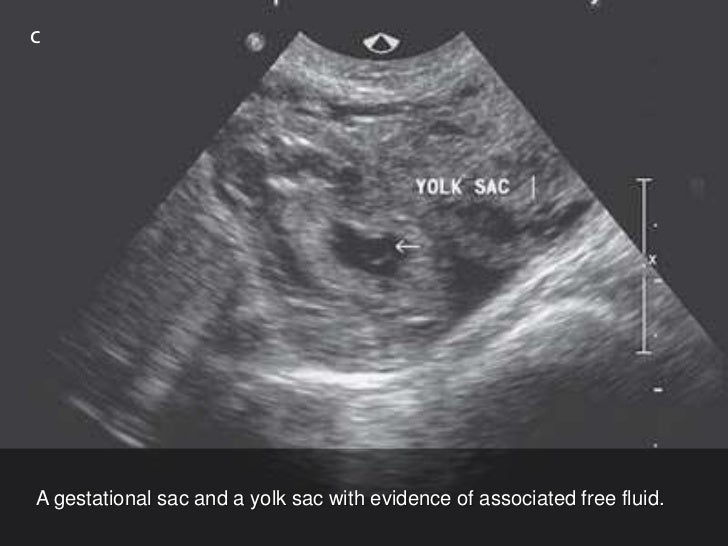

A sac-like structure in the uterus with a positive pregnancy test could represent an early gestational sac or a pseudogestational sac of ectopic pregnancy. Ectopic pregnancy potentially is life-threatening; therefore, making a timely diagnosis is critical.

The pseudogestational sac sign is a well described entity in the literature in the setting of ectopic gestation, and represents a decidual reaction surrounding intrauterine fluid/hemorrhage without a yolk sac or fetal pole [3,5,8]. As many as 1 in 10 ectopic pregnancies present with a pseudogestational sac.

The yolk sac is inside the gestational sac, a large cavity of fluid inside the uterus that surrounds an embryo. The yolk sac attaches to the outside of the developing embryo. The yolk sac must be inside the gestational sac, and the gestational sac must be inside the uterus.

generally irregularly-shaped with pointed edges and/or filled with debris, sometimes referred to as 'beaking'. centrally located in the endometrial cavity, rather than eccentrically located within the endometrium. displaces the anterior and posterior endometrial cavity surfaces. does not demonstrate a yolk sac.

As opposed to a normal gestational sac, a pseudosac is typically located centrally and may fill the entire endometrial cavity and it also lacks the “double ring” sign. True gestational sacs will usually be slightly off-center and will have a detectable double decidual sign. True sacs also will eventually develop an internal yolk sac later followed by an embryo, but pseudosacs will have neither.

The sonogram shows a sac in the uterus but this is not a normal gestational sac or a normal pregnancy. The presence of a pseudosac rather than a true gestational sac means that the pregnancy is likely elsewhere, or ectopic. Pseudosacs occur in about 10% of ectopic pregnancies and can lead the ultrasound technician, the radiologist, or the treating provider astray if they are identified as a sign of a normal pregnancy and not seen for what they truly are-a potential red herring.

A yolk sac, which indicates a viable pregnancy, is usually seen within the gestational sac by 35 days gestation. 8 One of the more common types of miscarriages—known as an anembryonic pregnancy, empty sac, or blighted ovum—happens when a gestational sac does not contain an embryo. In other words, an embryo failed to develop. 9

The yolk sac is inside the gestational sac, a large cavity of fluid inside the uterus that surrounds an embryo. The yolk sac attaches to the outside of the developing embryo. The yolk sac must be inside the gestational sac, and the gestational sac must be inside the uterus. Otherwise, this can indicate the pregnancy has failed or will fail.